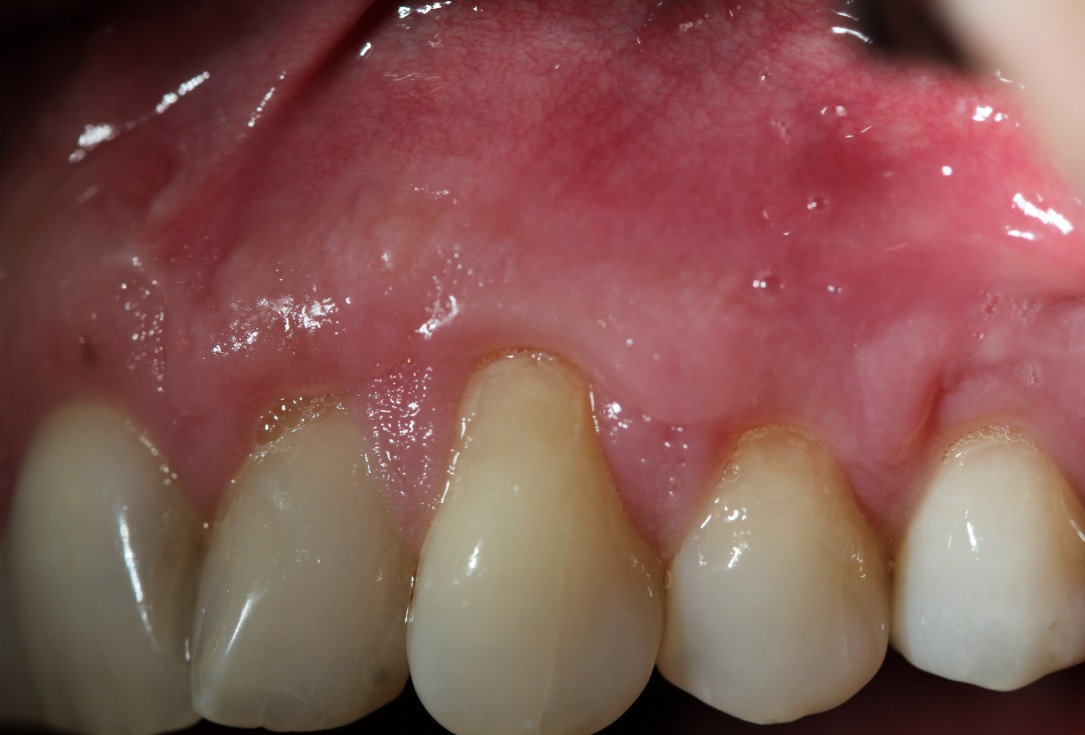

Multiple gingival recessions treated by MCAF in conjunction with mucoderm® - Kasaj

Pre-surgical clinical situation. Multiple adjacent gingival recessions at teeth 12,13 and 14.